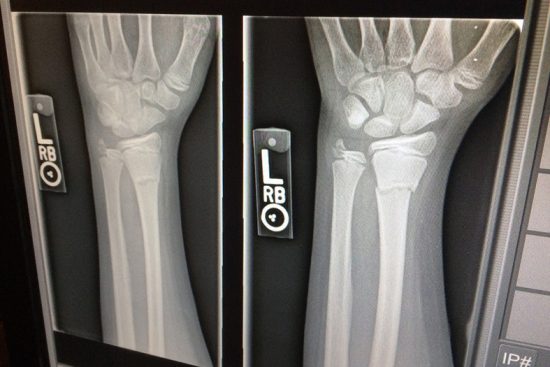

Ao procurar um ortopedista posteriormente, foi detectado uma fratura em três pontos do pulso esquerdo. Foto: Reprodução.

No local, foi realizado um exame de raio-x, onde a médica alegou que a paciente não havia quebrado o braço nem o pulso e receitou as medicações. Porém, as dores continuaram e a mulher decidiu procurar outra unidade de atendimento, onde um ortopedista identificou uma fratura em três pontos do punho esquerdo. A moradora então decidiu requerer a compensação por danos morais e materiais, já que o segundo médico informou que identificação tardia do trauma poderia dificultar a recuperação da paciente.